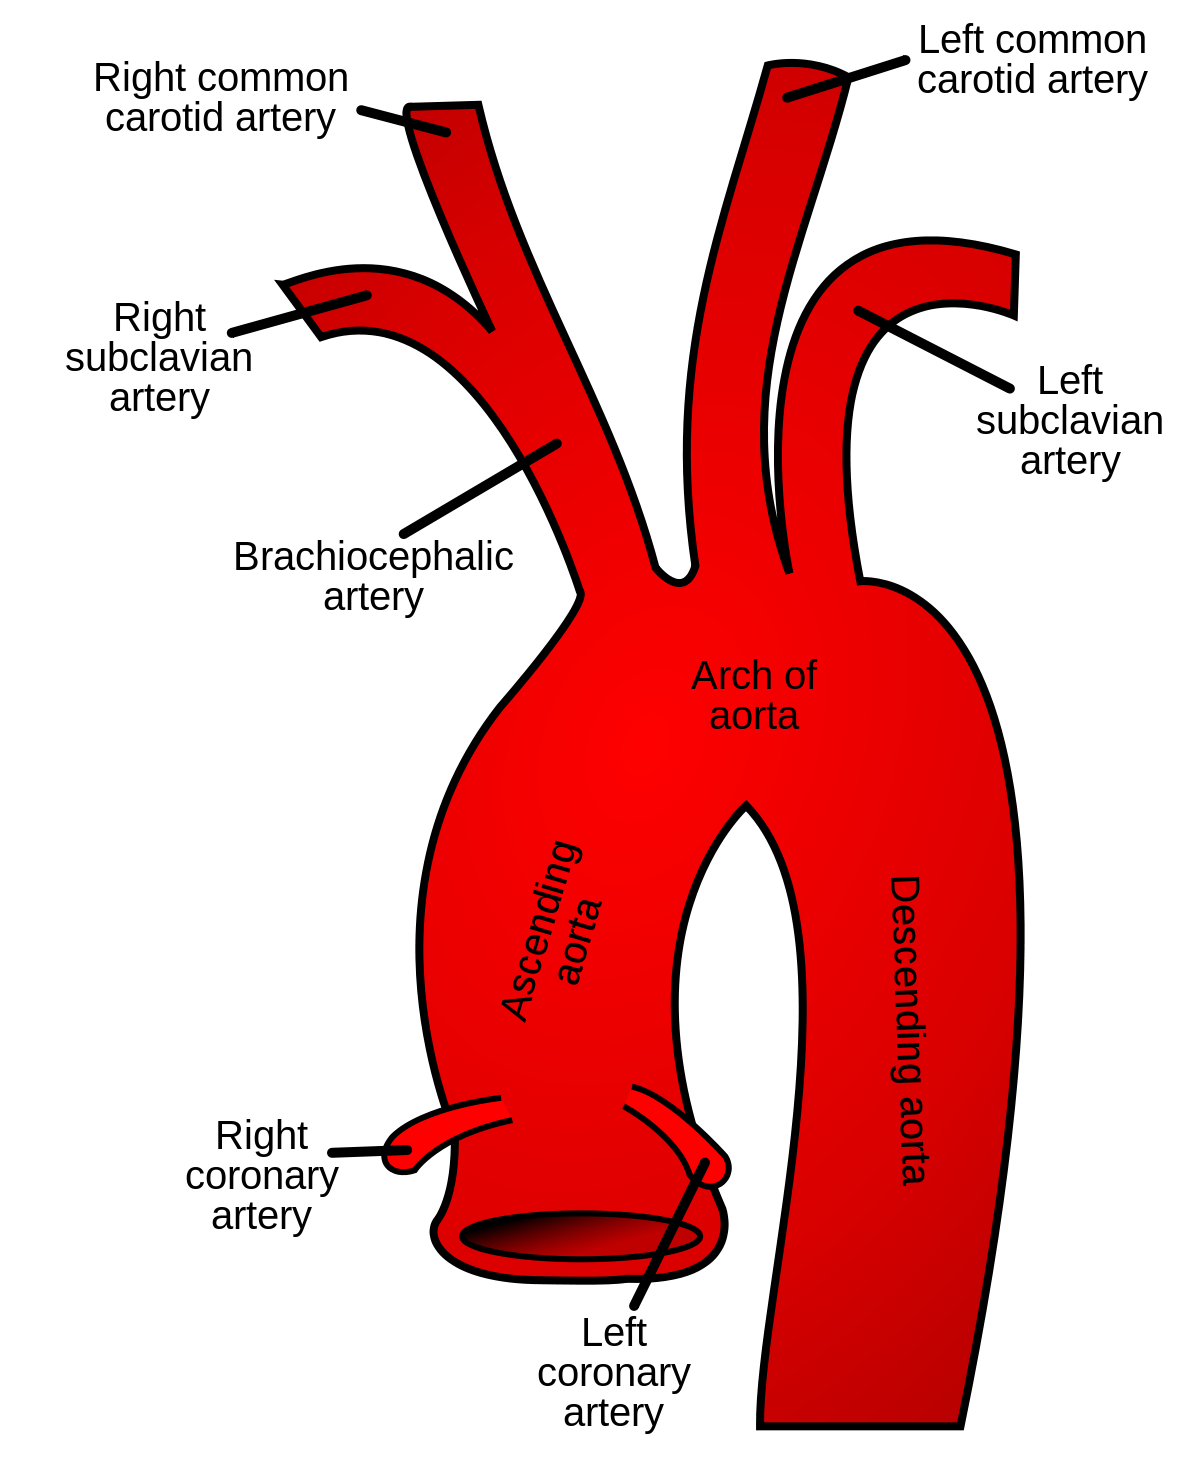

Subclavian a.

Thyrocervical trunk

Common carotid

Superior thyroid artery

Internal carotid a.

- left: arch of aorta

- right: Subclavian a.